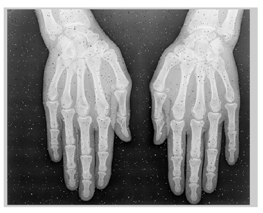

In this section, we present and analyze the results obtained with the proposed method, and compare it to methods proposed in similar works. The proposed watermarking system is implemented using MATLAB and executed on a Windows machine with the following characteristics: Intel R Core i5 processor, 4 GHz, 4 GB RAM, and Microsoft Windows 8 Professional operating system platform. In our experiments, we have used DICOM images of size 512 × 512 pixels as shown in Table 1.

Table 1.

Original images.

Table 2 shows the attacked watermarked image and the corresponding extracted attacked zero-watermarks.

Table 2.

Attacked watermarked images and their corresponding extracted attacked watermarks Wa1 et Wa2.

From Table 2 we can see the effect of the attacks on the original image, along with the variation of the extracted attacked watermarks. It is worth indicating that in the case of rotation attacks, the proposed method applies the inverse rotation to the image before extracting the watermark. We notice that the cropping left top corner attack is the attack that affects images the most.